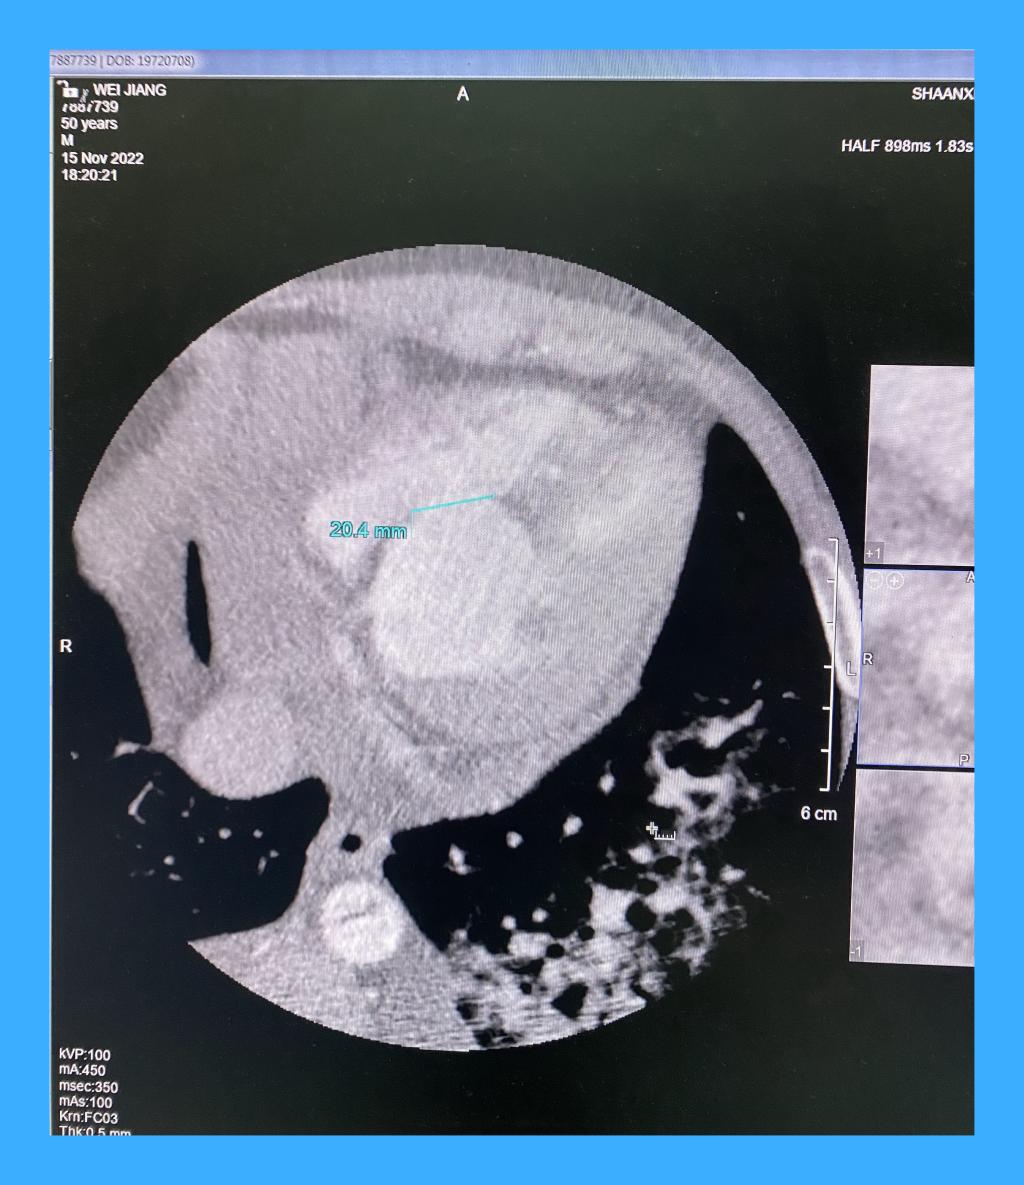

心脏外科,付建莉主任医师心脏超声检查,确诊为心脏左室下壁瘤样膨出,与正常室壁呈矛盾运动,测其瘤口为41mm,瘤深27mm,后室间隔下壁回声失落,左室面缺损口大小38mm,右室面缺损口大小21mm,病情十分危急。

心包切开后,发现大量血性心包积液,室壁瘤已经发生破裂,心脏严重水肿,经室壁瘤切口探查,发现一个近30毫米的巨大室间隔穿孔。术后经食道超声证实,室间隔穿孔消失,左心室前侧壁和下壁活动度改善,瓣膜未见反流。手术顺利结束,患者安全回到心外科ICU。